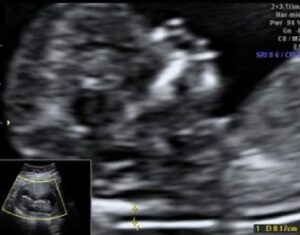

Στο κέντρο μας διενεργείται ο πλήρης υπερηχογραφικός έλεγχος που μπορεί να απαιτηθεί κατά τη διάρκεια της κύησης καθώς και επεμβατικός έλεγχος με βιοψία χοριακών λαχνών και αμνιοπαρακέντηση.

Όλες οι υπερηχογραφικές και επεμβατικές εξετάσεις πραγματοποιούνται σε ένα φιλικό και ήρεμο περιβάλλον με εξοπλισμό τελευταίας τεχνολογίας.